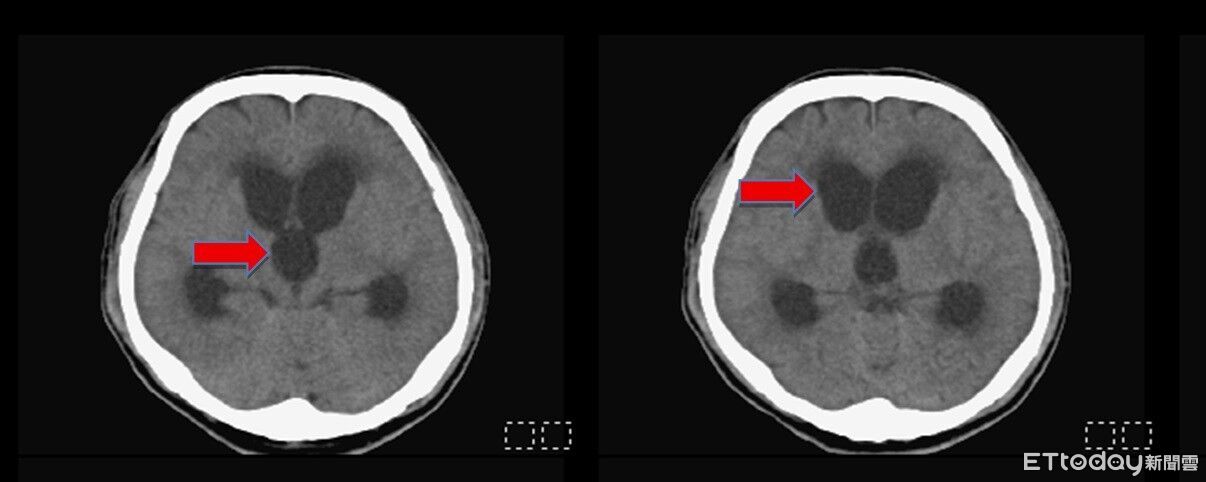

前台中市議長張宏年16日在家中被家屬發現沒有呼吸心跳,細察後驚覺辭世,享壽73歲。張宏年近年因服用盛唐中醫開立的硃砂中藥,鉛中毒導致腦部嚴重受損,家屬對死因有疑慮報請刑事相驗,檢方當日相驗後認死因不明,擇定今天(23日)解剖。台中地檢署表示,本案已於今上午完成解剖,後續將由法醫研究所進行解剖鑑定,釐清確切死因。